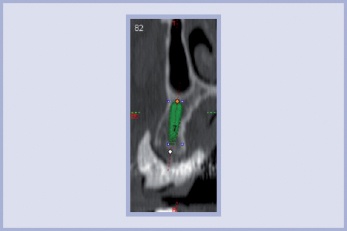

L’immagine TAC così ottenuta viene successivamente trasferita su supporto informatico CD leggibile con software dedicato Implant 3D (Media Lab srl – La Spezia) (figg. 2-6).

- Fig. 5